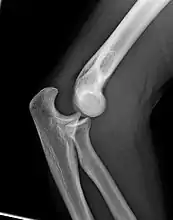

X-ray of ventral dislocation of the radial head. There is calcification of annular ligament, which can be seen as early as 2 weeks after injury.[29]